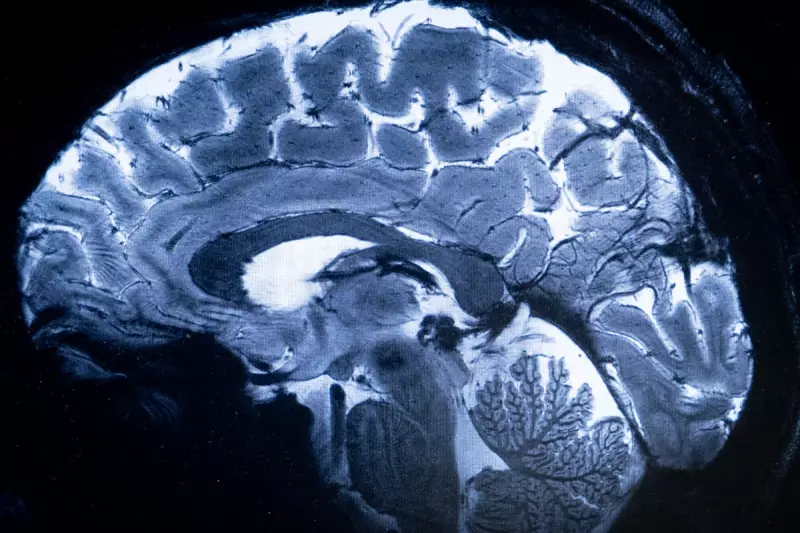

In a groundbreaking discovery, scientists have identified a potential cause of Alzheimer's disease linked to a deficiency in a crucial brain protein. This finding could pave the way for new treatments targeting the root of the condition.

Researchers have long struggled to pinpoint the exact mechanisms behind Alzheimer's, but this new study suggests that a lack of the protein RbAp48 in the hippocampus may play a significant role in memory loss and cognitive decline.